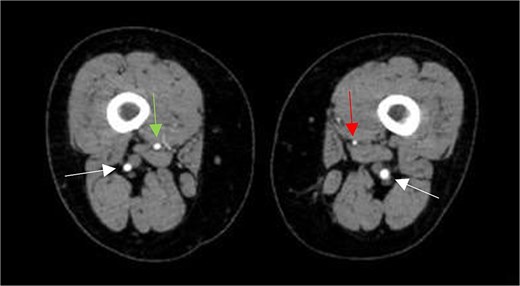

Subsequently, the patient underwent computed tomography angiography (CTA) of the lower extremities which revealed bilateral PSA (Fig. 1). The common femoral arteries trifurcated normally (Fig. 2), but the left superficial femoral artery (SFA) was significantly narrowed (Fig. 3). At the level of the knee, the right SFA joined the PSA to form the popliteal artery (Fig. 4). On the left side, the hypoplastic SFA converged with the PSA more proximally (Fig. 4); however, the artery was occluded, with no clear continuation into the popliteal artery (Fig. 4). Nevertheless, a markedly sub-occluded left popliteal artery was noted at the level of the fibular head, giving rise to a hypoplastic anterior tibial artery and tibio-peroneal trunk (Fig. 4). These findings align with Ahn-Min’s type I bilateral PSA (Fig. 5).

Axial CTA images show (A) the union of the left SFA and SFA; (B) occluded left popliteal artery; (C) the absence of the left popliteal artery and the emergence of the right popliteal artery from the union of right SFA and PSA; (D) the presence of a sub-occluded left popliteal artery (arrow on right leg) at the level of the fibular head and a normal right popliteal artery (arrow on left leg); and (E) the presence of hypoplastic left tibial and peroneal arteries (circles on left leg) along their course in the left leg compared to normal-sized arteries in the right leg (circles on right leg).